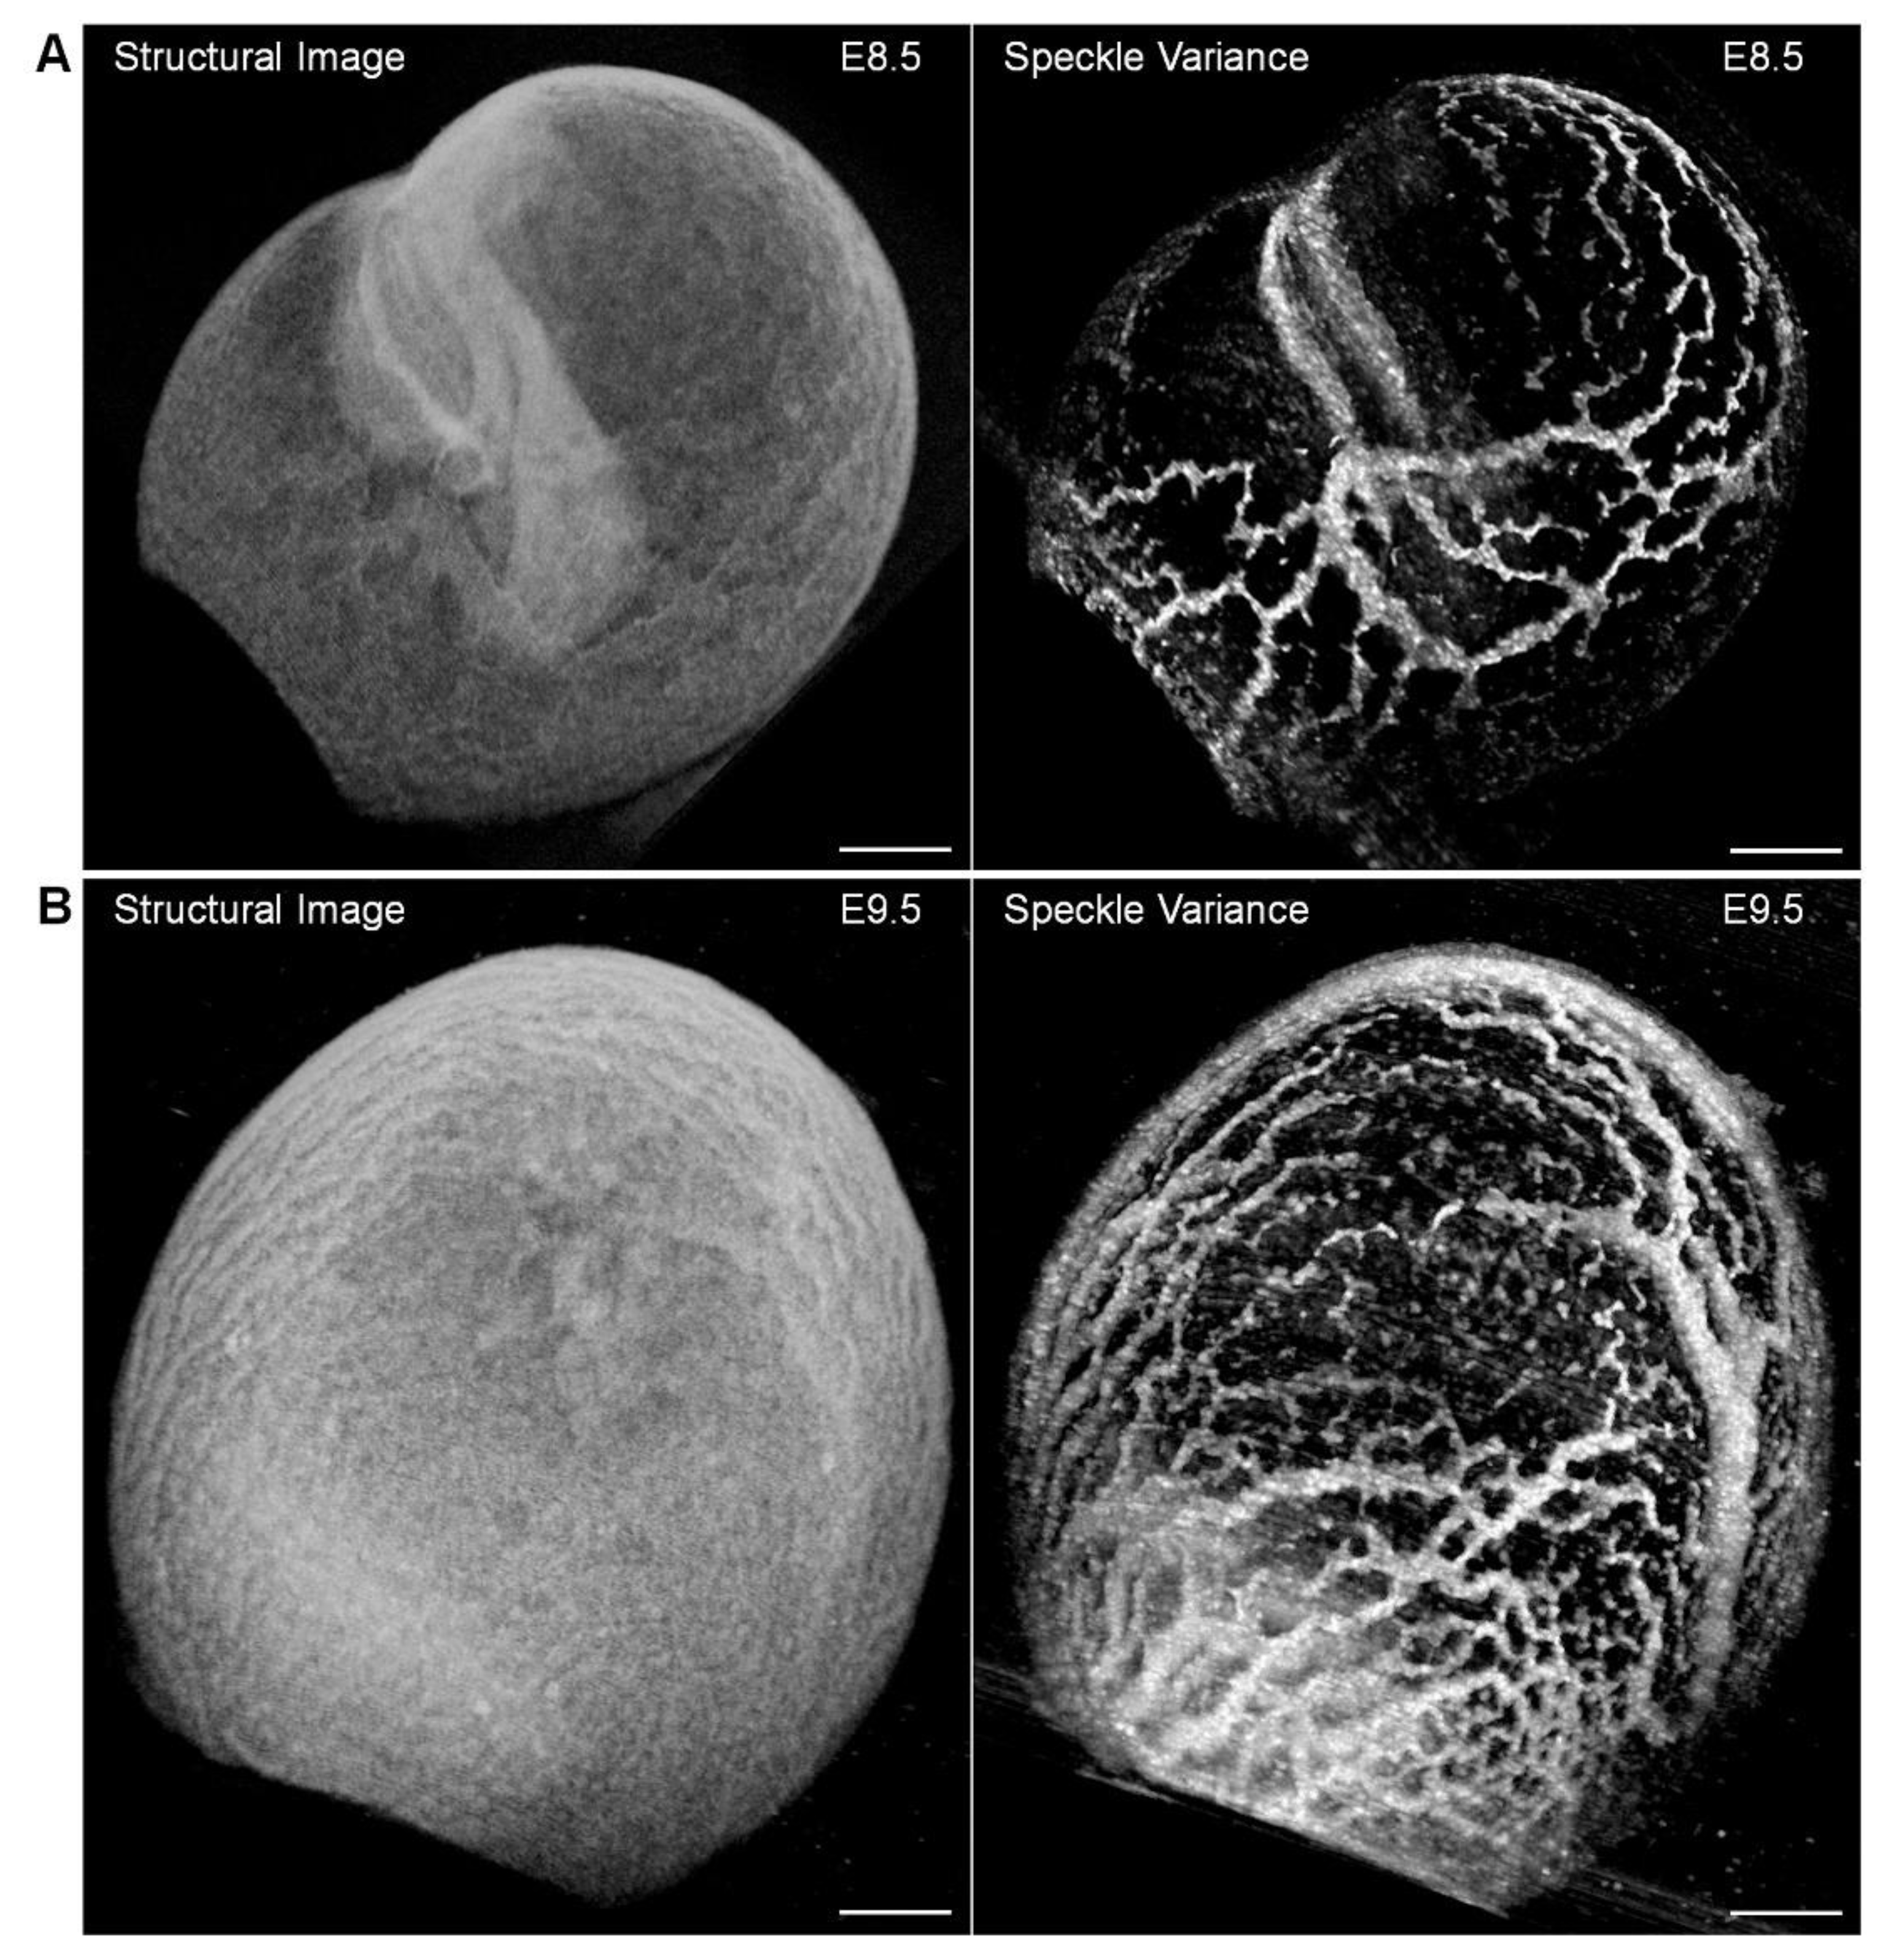

5. Hemodynamic Imaging with Doppler OCT

- Sudheendran, N.; Syed, S.H.; Dickinson, M.E.; Larina, I.V.; Larin, K.V. Speckle variance OCT imaging of the vasculature in live mammalian embryos. Laser Phys. Lett. 2011, 8, 247–252. [Google Scholar] [CrossRef]

- Grishina, O.A.; Wang, S.; Larina, I.V. Speckle variance optical coherence tomography of blood flow in the beating mouse embryonic heart. J. Biophotonics 2017, 10, 735–743. [Google Scholar] [CrossRef]

- Kulkarni, P.M.; Rey-Villamizar, N.; Merouane, A.; Sudheendran, N.; Wang, S.; Garcia, M.; Larina, I.V.; Roysam, B.; Larin, K.V. Algorithms for improved 3-D reconstruction of live mammalian embryo vasculature from optical coherence tomography data. Quant. Imaging Med. Surg. 2015, 5, 125–135. [Google Scholar] [CrossRef] [PubMed]